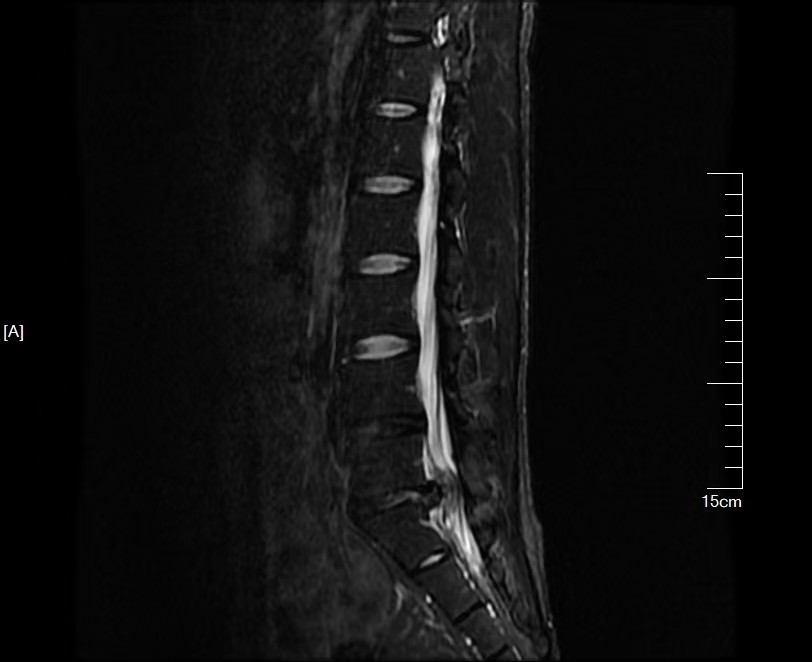

術前